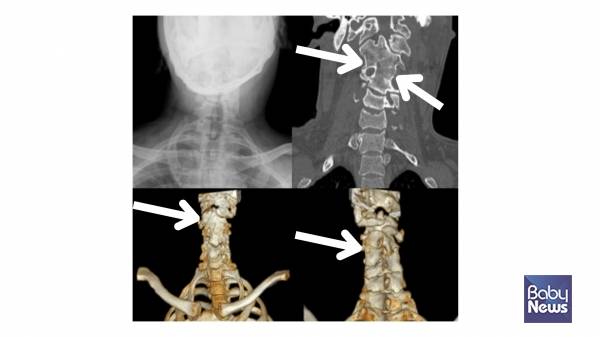

상사시나 안구 진탕(눈동자가 반복적으로 떨리는 상태로, 시야 안정에 영향을 줄 수 있는 증상) 같은 안과적 문제를 확인하는 것이 중요합니다. 또한, 척추 형성의 이상(예 반쪽 척추나 척추 분절 이상)으로 목이 기울어질 수 있습니다.

키아리 기형 1형(소뇌가 대후두공 아래로 내려오는 뇌 기형으로, 신경학적 증상을 유발할 수 있음)처럼 소뇌가 대후두공 아래로 내려오는 경우나 뇌종양 같은 중추 신경계 질환도 사경의 원인이 될 수 있습니다. 따라서 근성사경이 아니라는 이유만으로 '자세 문제'나 '습관'으로 단정하기보다는, 필요한 평가를 통해 기저 질환이 없는지를 확인하는 과정이 중요합니다.

치료받지 않은 근성사경은 성장하면서 다양한 2차 문제를 유발할 수 있습니다. 근성사경이 지속되면 얼굴 비대칭, 사두증, 척추측만증, 머리와 목이 만나는 부위의 비대칭까지 이어질 수 있습니다. 성인이 되어서도 목 통증과 자세 이상으로 고생하는 경우를 임상에서 적지 않게 보게 됩니다.